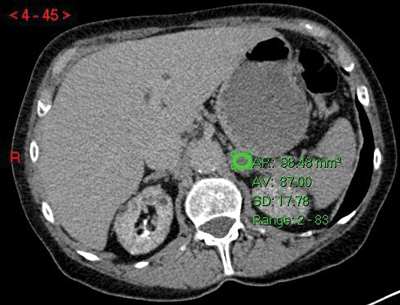

where E is the HU on the early post-IV contrast scan, D is the delayed scan and U is the unenhanced scan. A cut-off of >60% has been shown to diagnose a benign adenoma with a sensitivity of 88% and a specificity of 96% [5] (Figure 3).

Figure 3:

Top: Unenhanced CT (HU 23).

Centre: Arterial phase CT (HU 74).

Bottom: Delayed phase CT (HU 37).

Absolute washout = (74-37)/(74-23)x100 = 37/51x100 = 72.5% in keeping with adenoma.